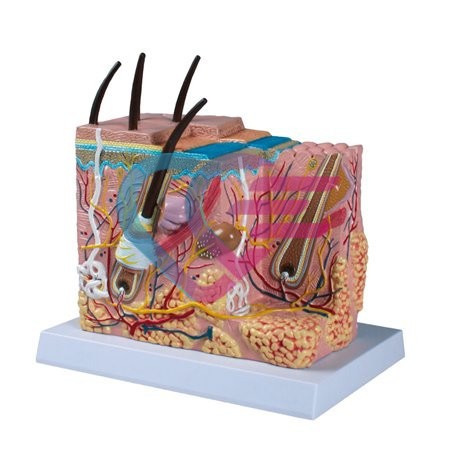

Povezani proizvodi